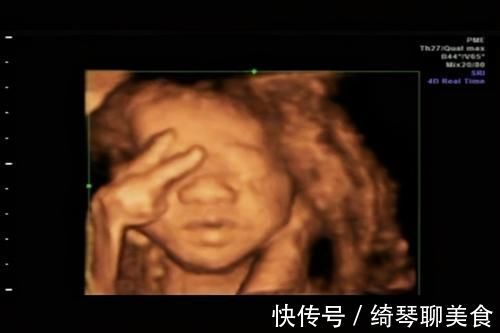

2、胎儿不配合

宝宝又不是成年人,能够配合医生摆出最好看的拍照pose,事实上他压根就不知道你们在干嘛,你们这边在拍照,他照样干自己的事情。

【 彩超|被宝宝的四维彩超照丑哭了?不是医生技术不好,而是有客观原因的】有可能用小手捂脸,把手举过头顶,甚至有可能故意“做鬼脸”,这些都会影响最终的图片效果。

如果想要拍出好看的照片,除非那个时候宝宝正处于精致状态,而是四肢都是放松的,没有遮挡住自己的小脸。